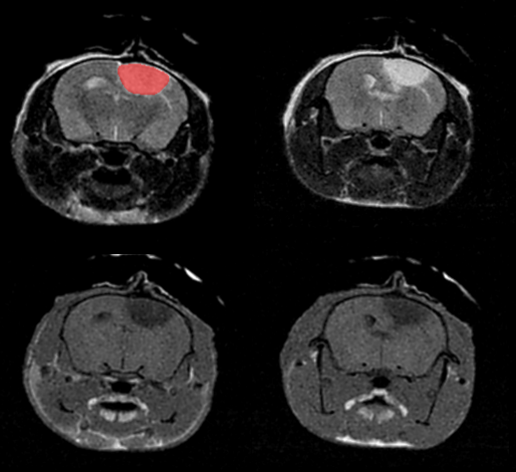

T2- (top row) and T1- (bottom row) weighted images show stroke lesion and its segmentation (in red) within the rat brain.

T2- (top row) and T1- (bottom row) weighted images show stroke lesion and its segmentation (in red) within the rat brain. Scintica Instrumentation Inc